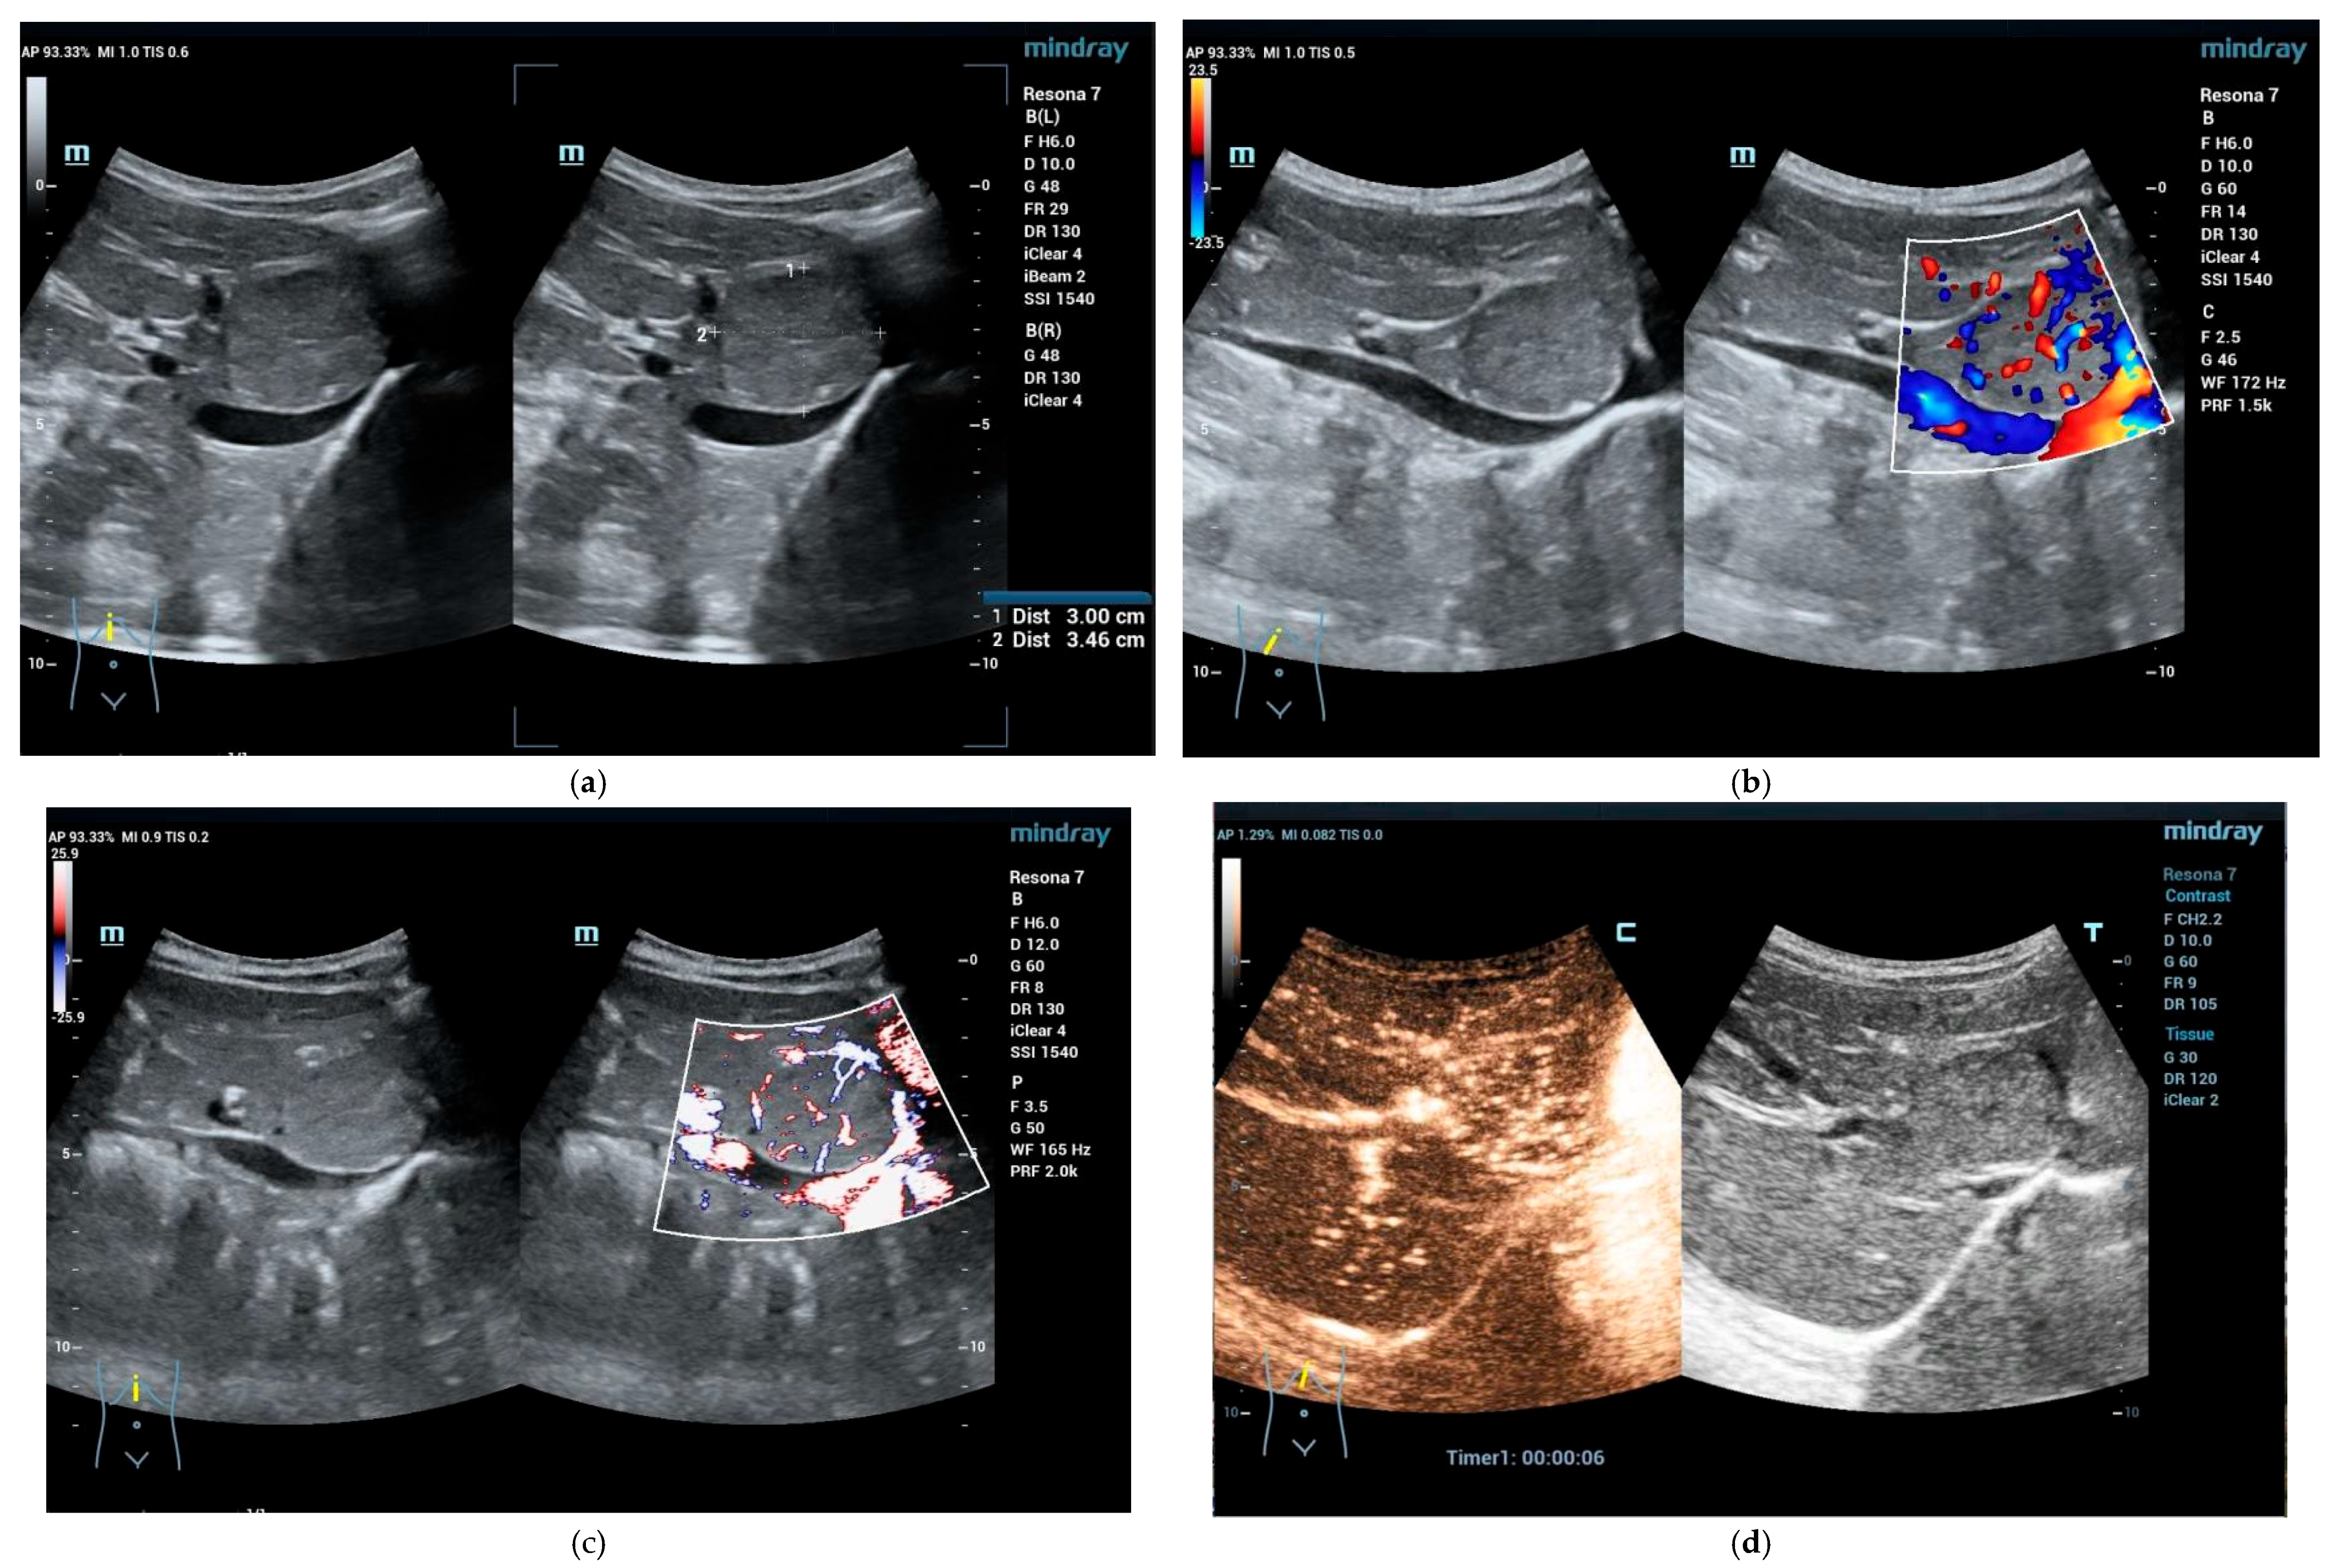

4.3.1. Hepatic Hemangioma

4.3.2. Congenital Hepatic Hemangioma

4.3.3. Infantile Hepatic Hemangioma